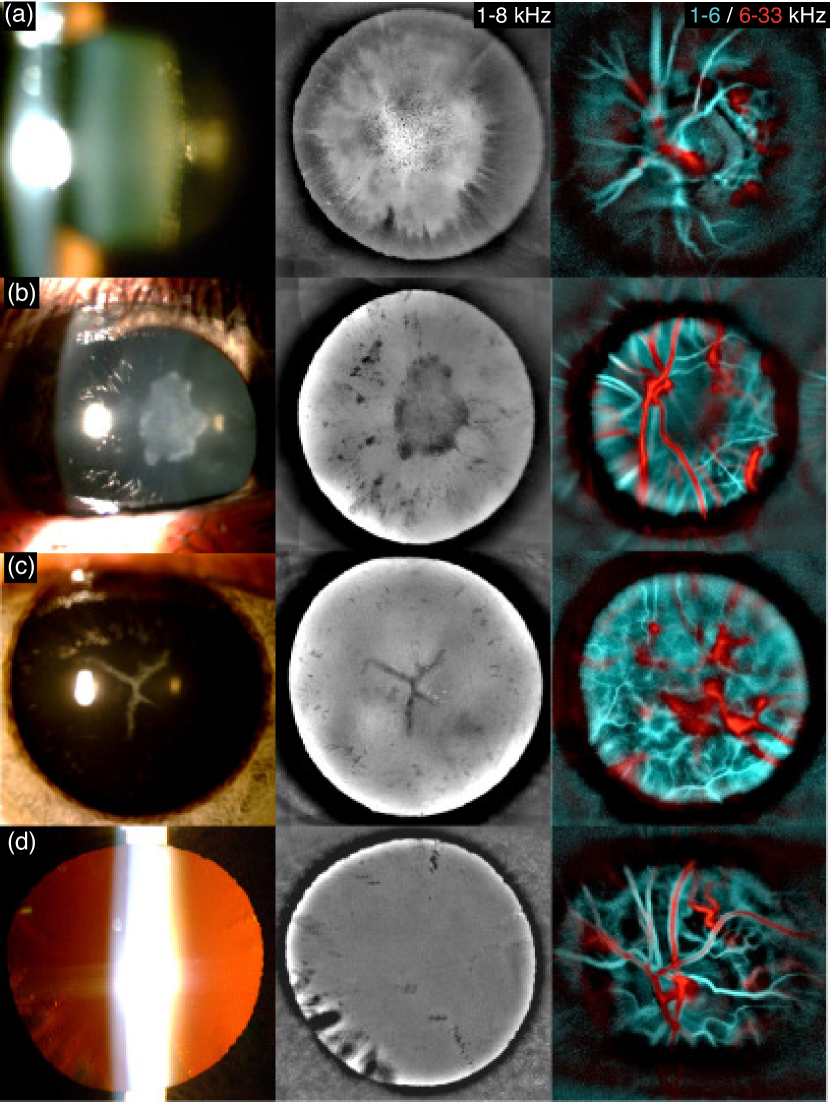

Figure 5: Imaging crystalline lens opacification with LDH. For each eye are shown the slit lamp examination (left), and from the same LDH data we computed the 1-8 kHz power Doppler image in the anterior segment (middle), and the slow/fast flow color composite image in the posterior segment (right). (a) Posterior subcapsular cataract. (b) Anterior polar cataract. (c) Star-shaped congenital cataract. (d) Presence of riders.

Power Doppler images of the anterior segment show the pupil area thanks to the defocused light from the retina. Because these images are formed with the SVD and Fourier analyses that aim at revealing blood flow, the optical field in the anterior segment comes from the defocused fundus vasculature. Depending on the imaged area and the power Doppler frequency range, that can include light scattered by retinal large vessels, unresolved capillaries, or in the choroid. The Doppler shifted light from the retina performs a retro-illumination of the anterior segment through the pupil, which can be used to reveal the transparency of the refractive elements of the eye. As the light from the retina goes through the lens and cornea, the transmitted optical field is modulated by the structures that absorb or scatter the light. These opacities can be revealed when computing power Doppler images from fundus holograms reconstructed in the pupil plane. This is illustrated in Fig. 5 where four eyes affected by different forms of cataract are documented with slit lamp images (left column) and LDH. From the same LDH data, we computed the 1-8 kHz power Doppler image in the anterior segment (middle column), and the color composite image of slow/fast flows in the posterior segment (right column).

The first example shows an eye affected by posterior subcapsular cataract, the second is an eye affected by anterior polar cataract, the third is a case of star-shaped congenital cataract, and finally in the last example there were riders (opacifications of the border of the lens oriented towards the lens center). In all examples LDH offers a better contrast than the slit lamp to delineate the opacities, which allows resolving smaller non-transparent features. LDH also presents the advantage of being able to image the eye transparency over the full extent of the dilated pupil without suffering from any specular reflection. Indeed, when imaging the anterior segment, ophthalmic instruments may suffer from strong corneal specular reflections. For example, slit lamp images are obtained with an oblique illumination to reduce specular reflection but they are still significantly affected by parasitic reflections that hide the contrast of the structures below them. However, LDH is able to bring a good contrast to the structures causing absorption of light over the full pupil without having any issue due to specular reflections thanks to optical and digital filtering. A polarizing beamsplitter cube is used to illuminate the eye with a linear polarization and only the cross-polarized light backscattered by the eye is transmitted to the camera. Therefore, the corneal specular reflection which preserves the initial polarization is optically rejected. Secondly, the Fourier filtering also ensures that the reconstructed light field is due to Doppler shifted light, which in the pupil area is the defocused light from the fundus. Indeed, the specular reflection should only be slightly Doppler shifted, and in case it is Doppler shifted due to the eye’s axial motion, then it should be rejected by the SVD filtering due to the high spatial coherence of the Doppler shift Puyo et al. (2020a).

In LDH pupil images shown in Fig. 5, no defocused retinal vasculature is seen, and there are probably several reasons for that. First, we used frequency ranges more favorable to having a more homogeneous illumination from the fundus. If using the 6-33 kHz power Doppler range (red part of the composite images), only the largest retinal vessels carrying the fastest flows are revealed in the retina. That would lead to a source of retro-illumination that would be very spatially localized, and the retinal structures would be much more visible in the pupil plane reconstruction. Using the 1-8 kHz (closer to the cyan part of the composite images) enables a much more uniform spatial distribution of energy in the fundus, and therefore to have less noticeable defocused retinal features in the pupil plane. Secondly, the effect of the cataract is simply more significant than the defocused vasculature. Also, we have here used mostly measurements where the optic nerve head (ONH) was imaged for the challenge of measuring the eye transparency at the same time as the ONH blood flow. However, imaging an area outside the ONH would be more favorable to having a homogeneous source of light from the retina. Finally, it should be mentioned that using a camera with smaller pixels is also expected to improve the defocusing of retinal features in the pupil plane, since smaller pixels enable a higher numerical aperture of the holographic detection, and therefore to reduce the depth of field of the reconstructed holograms Kreis (2006).